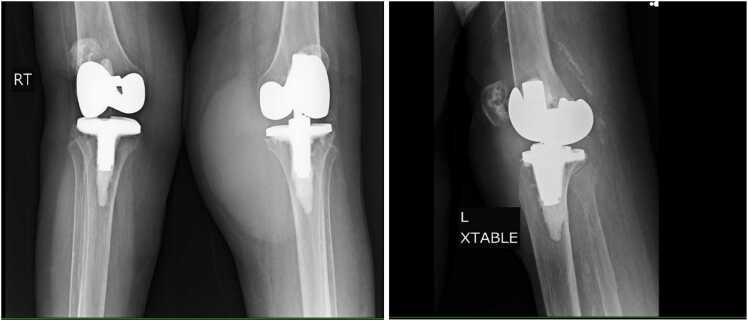

85岁女性,既往因骨关节炎行全膝关节置换术,左膝肿胀疼痛持续14个月。初步诊断为滑膜囊肿,她接受了多次检查和对症治疗,但没有好转。重复关节穿刺显示WBC为56000 /μL,中性粒细胞占61% %,淋巴细胞占34% %。滑液细菌和真菌培养均为阴性。抗酸杆菌(AFB)培养显示结核分枝杆菌复合体,并通过基质辅助激光解吸/电离飞行时间(MALDI-TOF)质谱法证实。本病例强调了诊断膝关节疼痛的老年人结核性假体关节感染的挑战。

An 85-year-old woman with a history of total knee replacements for osteoarthritis in the past, presented with left knee swelling and pain that persisted for 14 months. An initial diagnosis of synovial cyst was made, and she underwent multiple aspirations and symptomatic treatments without improvement. Repeat arthrocentesis showed a WBC of 56,000/μL with 61 % neutrophils and 34 % lymphocytes. Synovial fluid bacterial and fungal cultures were negative. The acid-fast bacilli (AFB) culture revealed the Mycobacterium tuberculosis complex and was confirmed by matrix-assisted laser desorption/ionization time-of-flight (MALDI-TOF) Mass Spectrometry. This case highlights the challenges of diagnosing tuberculous prosthetic joint infection in an elderly individual with knee pain.